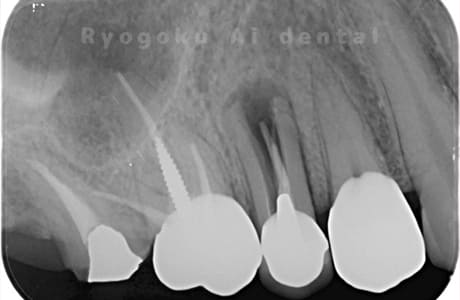

Case07

- 原因

- 右下6番歯根破折

-

- 治療内容

- インプラント治療

- 治療費用

- 約600,000円

右下の腫れが治らないとの事でご来院された患者様です。歯が割れていたため、抜歯を行い、骨に代わるお薬を入れ、インプラントを埋入致しました。経過良好で大変満足していただけました。

<リスク・副作用>

治療後、痛みや違和感、出血、腫れなどが出る事があります。喫煙者、糖尿病などの方の場合、歯が生着しない場合があります。